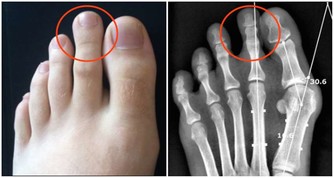

1.脂肪墊勞損 脂肪墊充填於膝關節前部的間隙,有加強關節穩定和減少摩擦的作用。脂肪墊勞損的發病原因可能是由於外傷或者是長期摩擦引起脂肪墊充血、肥厚並發生炎症,與髕韌帶發生粘連,從而使膝關節活動受限。這種損傷多發生於經常步行、登山或者蹲起運動較頻繁的30歲以上人群。患者會覺得膝關節疼痛,完全伸直時疼痛加重,但關節活動並不受到限制。勞累後症狀明顯。治療以保守治療為主,配合理療及口服藥物。 2.半月板損傷 半月板損傷是運動員的一種常見損傷,在下肢負重,足部固定,膝關節微屈時,如果突然過度內旋伸膝或外旋伸膝(例如排球運動中,隊員在防守時突然轉身魚躍救球的動作),就有可能引起半月板撕裂。半月板損傷會有明顯的膝部撕裂感,隨即關節疼痛,活動受限,走路跛行。關節表現出腫脹和滑落感,並且在關節活動時有彈響。治療需根據損傷程度決定保守治療還是手術治療。 3.膝關節創傷性滑膜炎 膝關節滑膜是組成膝關節的主要結構之一。滑膜細胞分泌滑液,可以保持關節軟骨面的滑潤,增加關節活動範圍。由於外傷或過度勞損等因素損傷滑膜,會產生大量積液,使關節內壓力增高,如不及時消除,則很容易引起關節粘連,影響正常活動。患者會感覺膝關節疼痛、腫脹、壓痛,滑膜有摩擦發澀的聲響。疼痛最明顯的特點是當膝關節主動極度伸直時,特別是有一定阻力地做伸膝運動時,髕骨下部疼痛會加劇,被動極度屈曲時疼痛也明顯加重。治療多以保守治療為主。 4.膝關節骨性關節炎 這種病症多見於中老年、女性居多,超重負荷是致病的主要原因。膝關節會腫脹而疼痛,有時活動關節會有摩擦音。膝部可能出現內翻畸形並伴有內側疼痛。治療根據關節蛻變情況選擇是否行關節置換的治療,目前膝關節骨性關節炎的關節置換治療是國際上較成熟的治療方式。 5.膝關節韌帶損傷 膝關節微屈時的穩定性相對較差,如果此時突然受到外力導致外翻或內翻,則有可能引起內側或外側副韌帶損傷。臨床上內側副韌帶損傷占絕大多數。以這種損傷為例,患者會有明確的外傷史,膝關節內側疼痛、壓痛,小腿被動外展時疼痛加劇,膝內側有腫脹,幾天後會出現瘀斑。膝關節活動會受到限制。 6.寒冷 在日常生活中,多數關節疼痛並不是由外傷引起的,寒冷(特別是持續受涼和巨大的溫度反差)才是造成關節疼痛的主要原因。隨著社會的發展,人們的審美觀、生活習慣發生了很大的變化,人們更加注重形態美。即使是在寒冷的冬季,很多人也不再身著厚厚的棉服,而是儘可能地減輕身上的負擔,以適應現代審美觀念及快速的生活節奏。但是在體驗美感的同時,人們不得不付出關節損害的代價,因為寒冷可導致肌肉和血管收縮,引起關節疼痛。 7.運動不當 有些老年人喜歡登山,但如果沒做好準備活動或運動量太大,也可造成關節疼痛。特別是身患關節滑膜炎或骨性關節炎的人,更容易引起關節疾病發作或加重。在登山運動中,下山時,全身的重量完全加在一側膝關節上,膝關節承受的壓力是正常站立時的數倍。人們上下樓梯時,也會出現同樣的情況。 8.不良走路習慣 例如經常穿著不合腳的鞋或穿著拖鞋、高跟鞋長距離行走,會使膝關節長時間處於非正常的受力狀態,造成膝關節慢性損傷,引起疼痛。 9.風濕,類風濕,強直性脊柱炎,紅斑狼瘡等免疫性疾病引起的膝關節病變。 10.代謝性疾病如「痛風」引起的膝關節疼痛發病率有明顯的上升趨勢。 #如常老年專用中藥熱敷包#